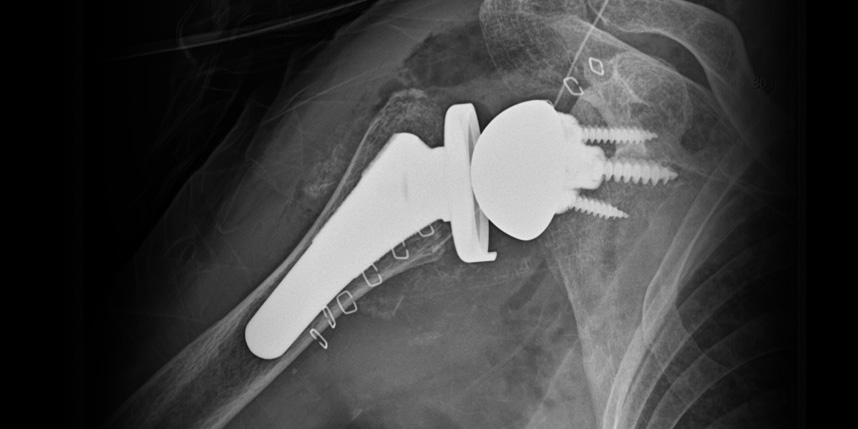

역행성 인공관절 전치환술

역행성 인공관절 진치환술

(회전근개 심한 파열 및 관절염 진행)